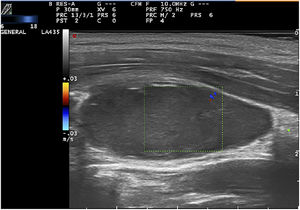

Ante las dudas diagnósticas, se decidió realizar una ecografía cutánea con sonda lineal a una frecuencia de 15-18MHz con equipo Esaote Mylab en la que se apreció una estructura hipoecoica y ovalada, de bordes bien definidos, de 2,8×1,5×1,4cm, con eje mayor en sentido longitudinal, localizada por debajo del músculo esternocleidomastoideo. El modo Doppler color mostró una ausencia de vascularización intralesional, con presencia de vascularización periférica (figs. 2 y 3). Los hallazgos ecográficos fueron compatibles con un hematoma intramuscular.

Desde el punto de vista ecográfico, el diagnóstico diferencial de nuestra paciente incluyó el lipoma, las adenopatías y la trombosis. Los lipomas presentan una ecogenicidad variable y en ocasiones un bandeado hiperecogénico característico. Tienden a localizarse en el tejido celular subcutáneo y sus límites a menudo no están claramente delimitados. Las adenopatías suelen presentar morfología ovalada, centro hiperecoico y halo hipoecogénico periférico, aunque en estados inflamatorios se puede observar un aumento de volumen y vascularización, si bien conservan su morfología y ecoestructura. Las trombosis son lesiones habitualmente hiperecogénicas, en el interior de los vasos, que pueden presentar vascularización periférica (recanalización). El hematoma se manifiesta ecográficamente como una imagen hipoecoica o anecoica, sin flujo sanguíneo en su interior, pero con vascularización dópler periférica6. Esta última descripción coincidió con los hallazgos ecográficos de nuestra paciente.